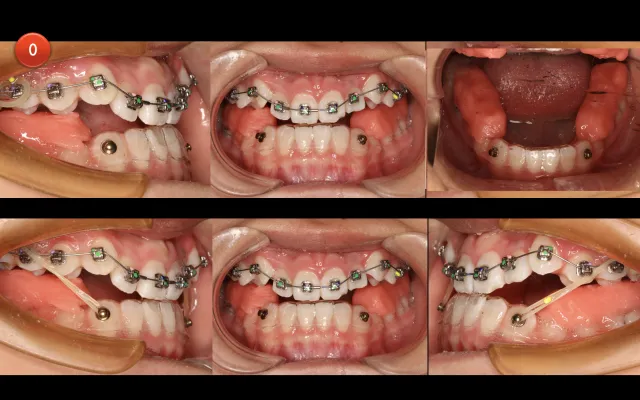

支抗钉操作理论及各部位植入技巧

1.支抗钉概论

2.支抗钉植入方式方法(含大量真实操作视频)

3.颧牙槽嵴下区骨钉案例(骨性II类上颌突)

4.下颌外斜线骨钉案例(骨性III类上颌突)

5.骨钉在非拔牙矫治中的应用

二次矫治侧救赎—骨钉

1.骨钉控制垂直向

2.骨钉控制矢状向

3.骨钉辅助上下颌牙列远中移动

4.骨钉如何解除“过山车”

骨钉实操